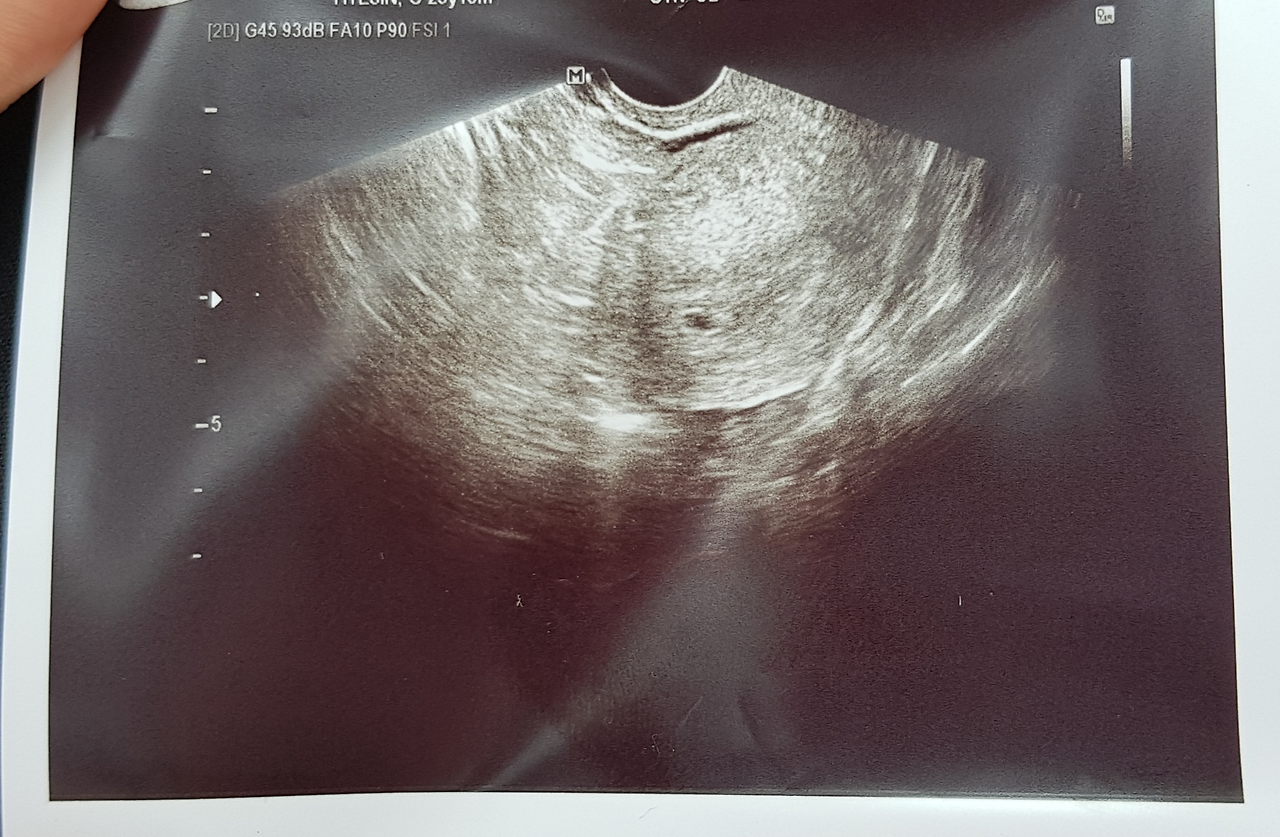

너무 작아서 화면 오류처럼 보였던 첫 초음파

[임신 맞네요. 축하드려요.]

요기 요 작은 거, 요게 아기집입니다. 바라던 말이 들려오던 순간이었다. 모니터에는 하얗고 까만 얼룩들 사이에 콩만 한 점 한 개가 콕 박혀있었다. 너무 작아 사실은 화면에 오류가 난게 아닌가 했지만 선생님은 그 작디작은 것이 곧 자라 아기가 될 것이고, 착상이 잘 됐다는 말까지 덧붙였다. 일주일 내내 해댄 마음고생을 생각하면 임신이라는 말을 듣자마자 왈칵 눈물이라도 쏟지 않을까 했었는데, 정작 내 마음은 얼떨떨했다.